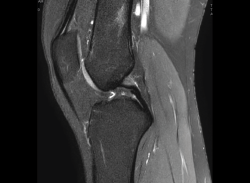

Resonancia magnética

Se basa en la propiedad que poseen los núcleos de hidrógeno de absorber energía electromagnética cuando están sometidos a un campo magnético intenso. La RM representa un mapa de la densidad de protones, o sea, de la distribución de agua por el organismo(12).

Se consiguen unas imágenes de alta resolución para la valoración de meniscos, ligamentos y tendones. Además, es especialmente útil en las rodillas operadas, lesiones tumorales, evaluación del cartílago y la visualización de los nervios(13).

1. Estudio de las estructuras intraarticulares

Es la prueba no invasiva de elección para valorar las lesiones internas de la rodilla(2). Aunque el estudio por RM es a menudo considerado como la prueba diagnóstica de elección para la detección de alteraciones meniscales, se asocia en ocasiones con errores diagnósticos(16).

1.1. Meniscos

Figura 30. Corte de secuencia sagital T2 Fat-Sat de resonancia magnética de rodilla: menisco externo normal.

Se identifican como estructuras hipointensas en todas las secuencias, con asta anterior y posterior de morfología triangular.

Figura 31. Corte de secuencia sagital T2 Fat-Sat de resonancia magnética de rodilla: menisco interno normal.

La RM es la técnica de elección en el diagnóstico de la patología meniscal(17)(Figuras 30, 31, 32, 33, 34 y 35).